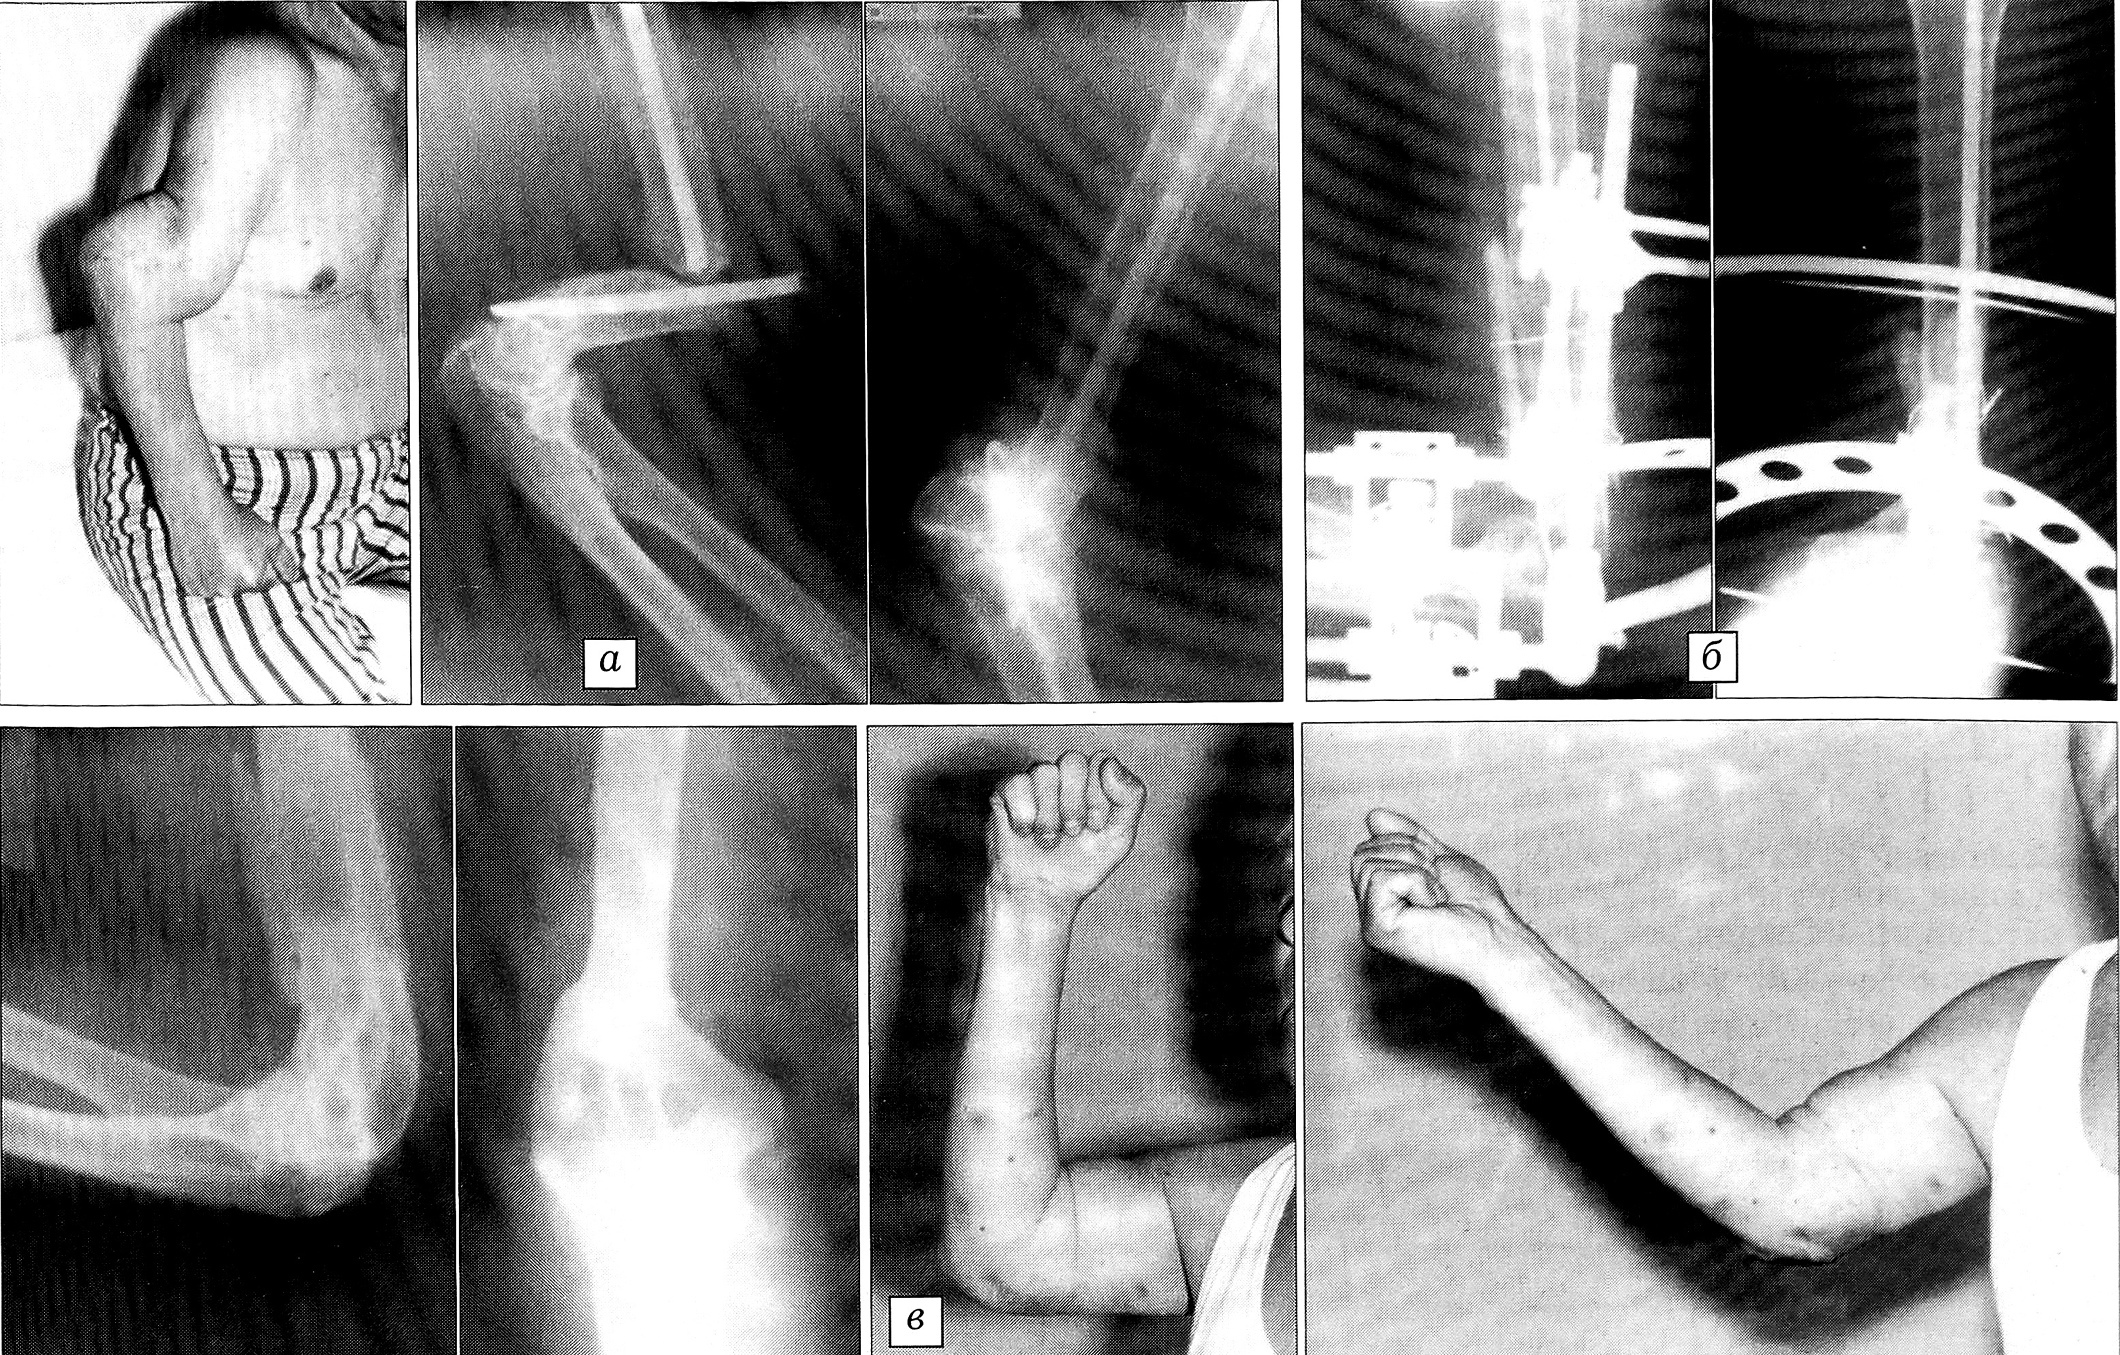

Пример 6. Больной К., 52 лет, упал на руку, получил закрытый перелом правой плечевой кости. В больнице по месту жительства через 5 дней произведен остеосинтез металлическим штифтом. Штифт сломался, сращения перелома не наступило. При обращении в ЦИТО через 11 мес после травмы: мышцы правого плеча атрофированы, по наружной поверхности плеча имеются рубцы, на рентгенограммах — ложный сустав плечевой кости (рис. 6, а). Учитывая сложность ложного сустава, после удаления сломанного штифта в костномозговой канал плечевой кости вновь введен штифт и наложен шарнирно-дистракционный аппарат, при помощи которого осуществлялась фиксация костных отломков с взаимным давлением (рис. 6, б) с одновременной разработкой движений в локтевом суставе. Через 5 мес клинически и рентгенологически отмечено сращение перелома и восстановление движений в локтевом суставе. Аппарат удален (рис. 6, в).

Рис. 6. Пример 6.Больной К., ложный сустав плечевой кости через 11 мес после интрамедуллярного остеосинтеза штифтом, перелом штифта и смещение костных отломков.а — при поступлении в ЦИТО; б — произведены повторный остеосинтез штифтом, костная пластика, наложен аппарат наружной фиксации; в — через 5 мес: перелом сросся, функция локтевого сустава восстановлена.